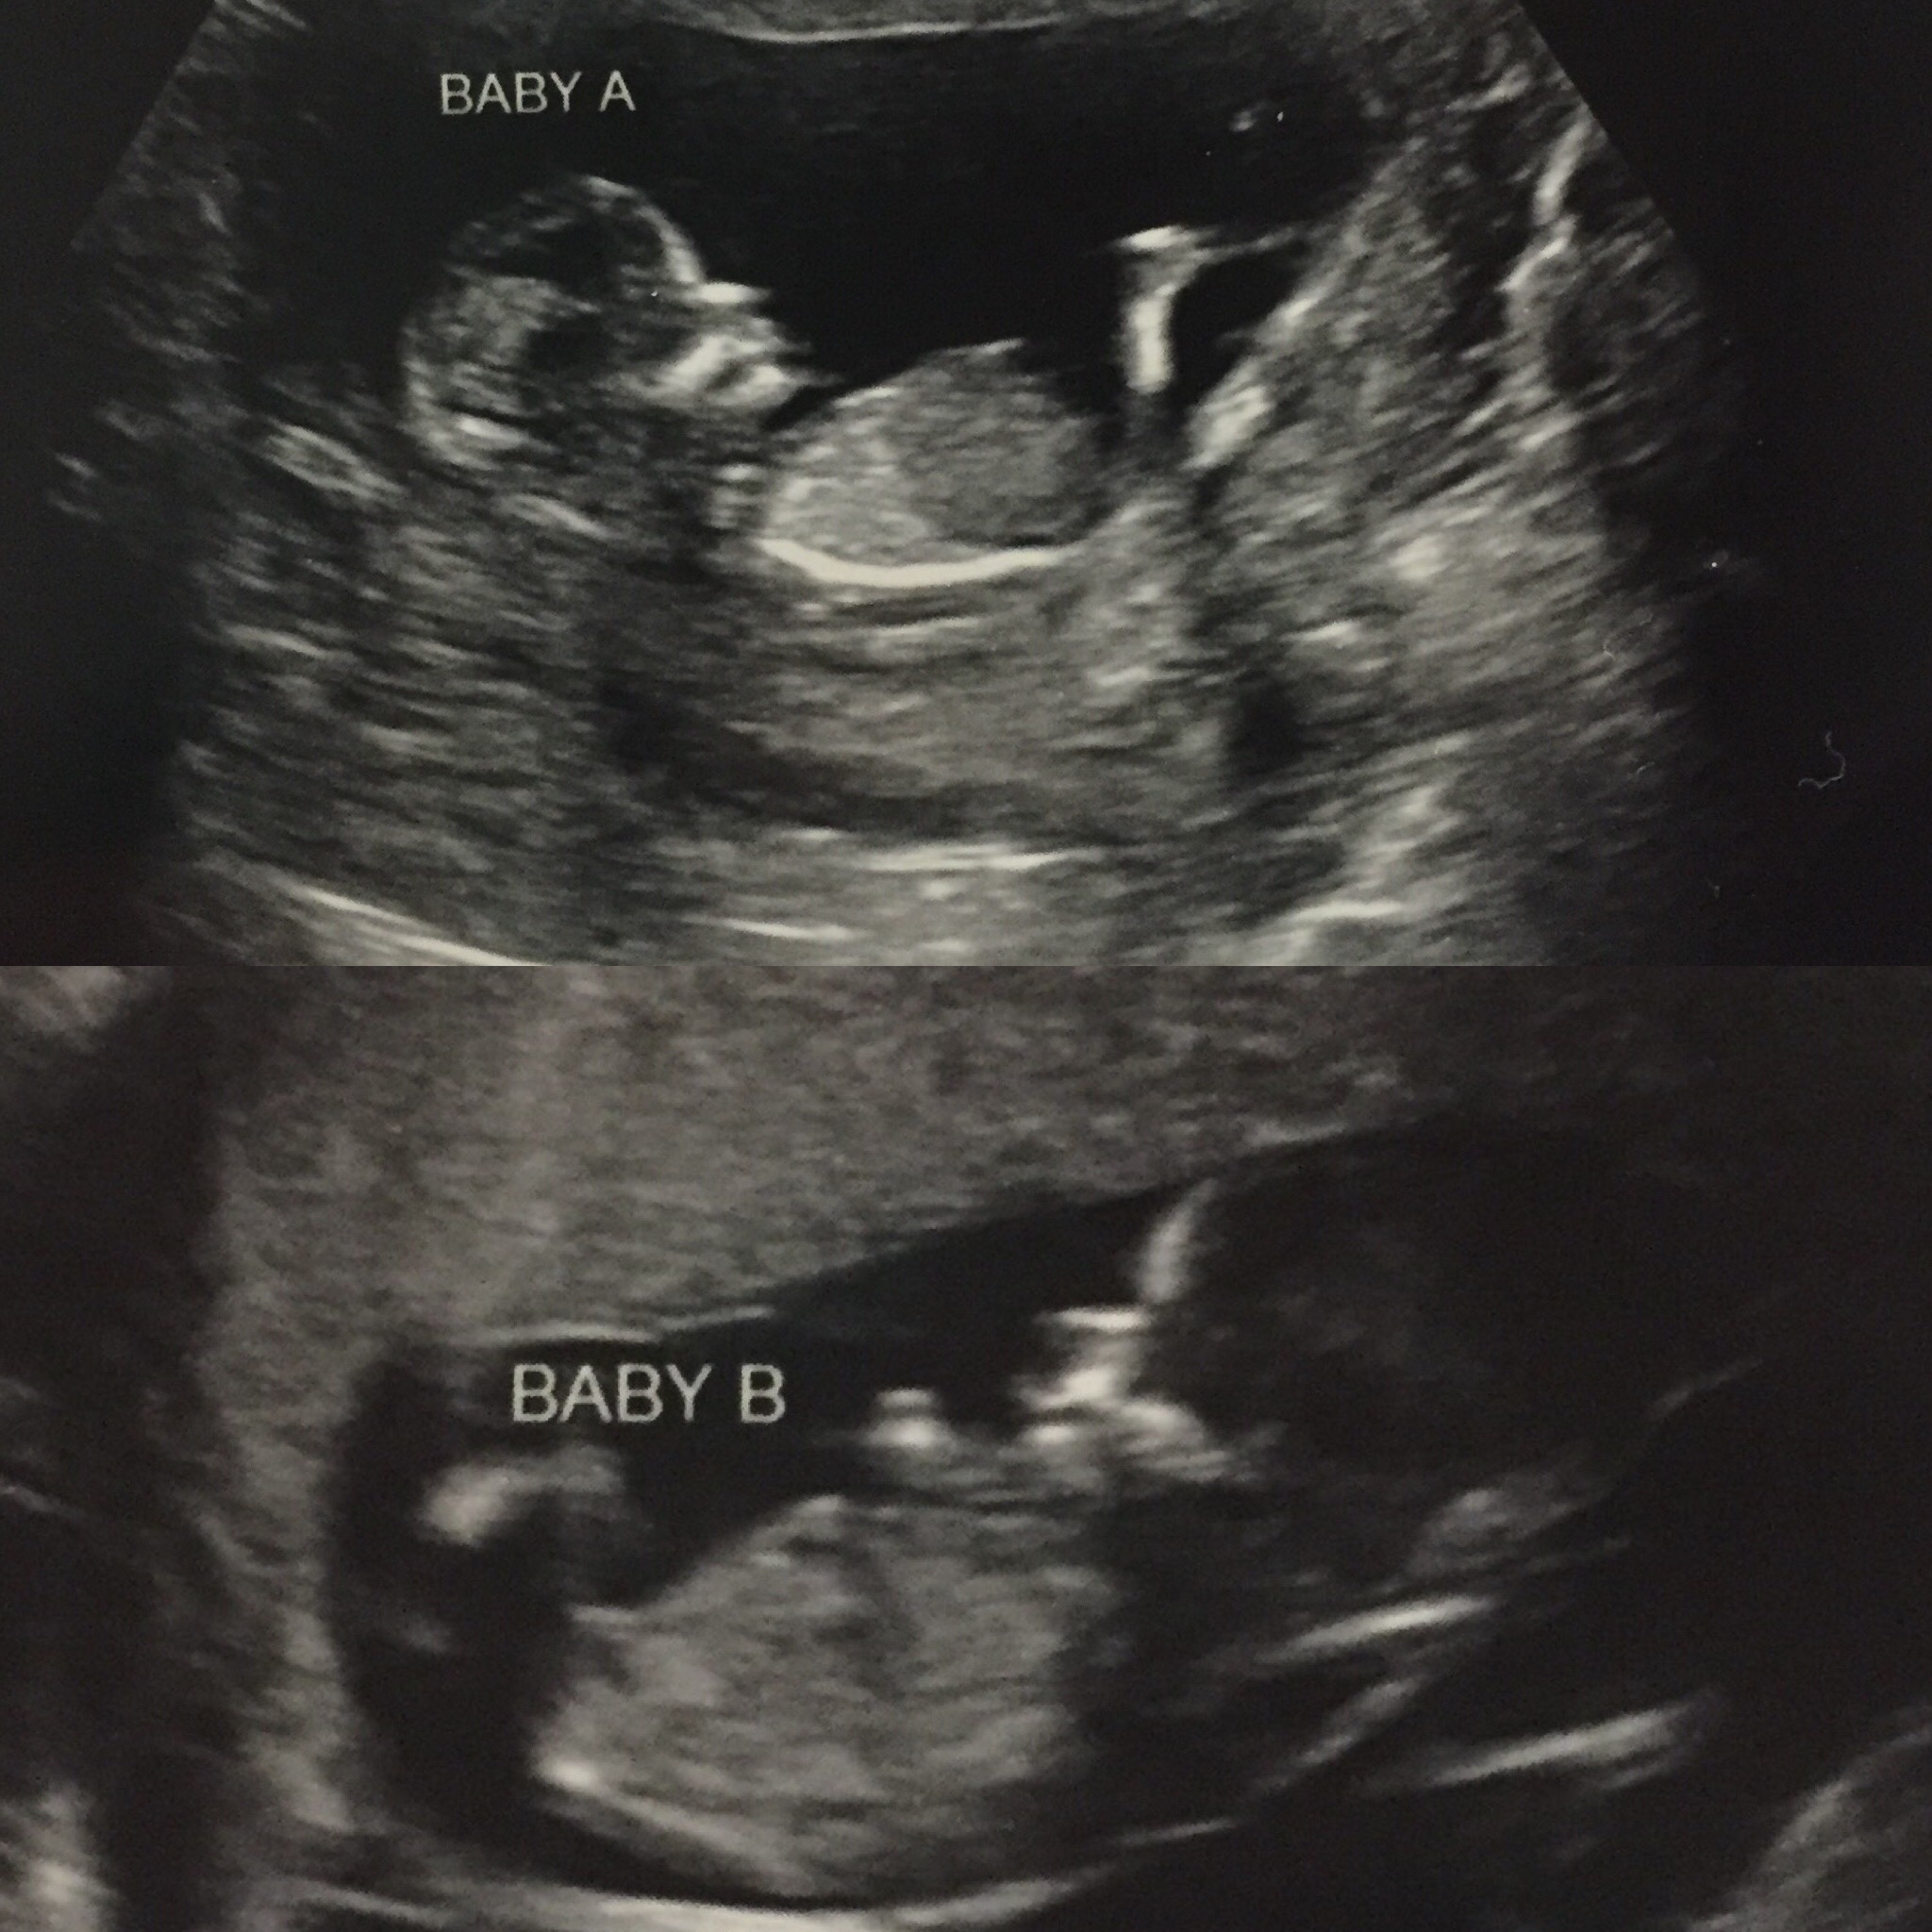

We finally got our first ultrasound on Monday. I'm so in love with our little kicker! They moved my due date up a day to May 27th. The heartbeat was 161 and my doc couldn't have been happier. (After all she's the one who had to tell us we might never have biological kids.) She insisted on doing the ultrasound herself which was wonderful.